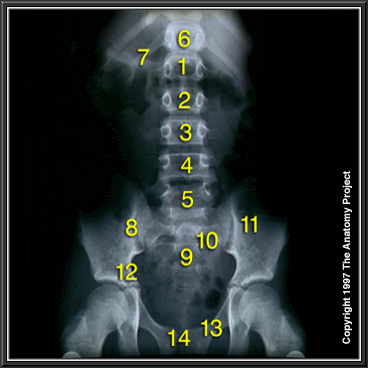

Abdomen, X-ray, Anteroposterior View

1st Lumbar vertebra

2nd Lumbar vertebra

3rd Lumbar vertebra

4th Lumbar vertebra

5th Lumbar vertebra

T12

Twelfth rib

Sacroiliac joint

Sacrum

Sacral foramen

Ilium

Pelvic brim

Superior ramus of pubic bone

Pubic symphysis